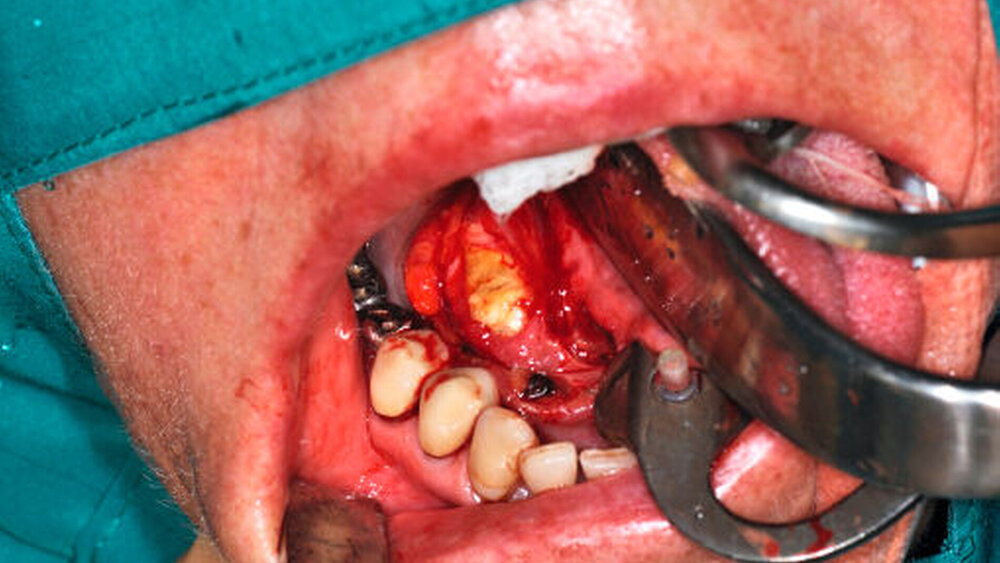

Die Antikoagulation wurde unverändert weitergeführt, wobei der Eingriff am Morgen vor der Einnahme der nächsten Tablette stattfand. Nach Schienung des Warthon-Gangs via Kunststoffröhrchen zur Identifikation desselben erfolgten die Eröffnung des Ganges sowie die Darstellung und Bergung des Speichelsteins (Abbildungen 4 und 5) bei einer Größe von 2 cm x 1,3 cm. Das intraoperativ geborgene Konkrement (Abbildung 6) konnte eindeutig als Speichelstein (Sialolith) identifiziert werden. Eine weiterführende histopathologische Dignitätsklärung war nicht erforderlich. Der eröffnete Ausführungsgang wurde über nicht resorbierbare Nähte im Sinne einer Marsupialisation an den Mundboden angesteppt und so die neue Mündung nach proximal verlegt.